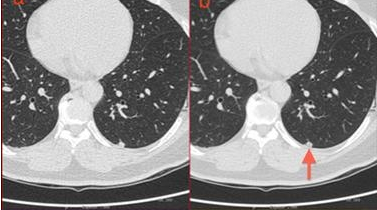

图2:肺内淋巴结